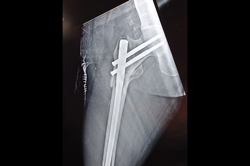

Scaphoid